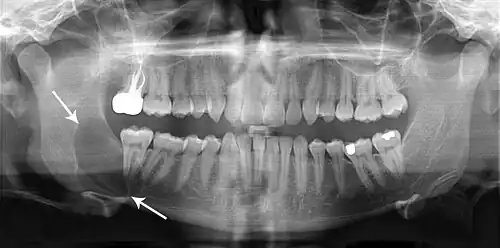

Radiographs of odontogenic keratocysts show well-defined radiolucent areas with rounded or scalloped margins which are well demarcated.[13] These areas can be multilocular or unilocular. The growth pattern of the lesion is very characteristic from which a diagnosis can be made as there is growth and spread both forward and backward along the medullary cavity with little expansion. No resorption of teeth or inferior dental canal and minimal displacement of teeth is seen. Due to lack of expansion of the odontogenic keratocyst, the lesion can be very large when radiographically discovered.[10]